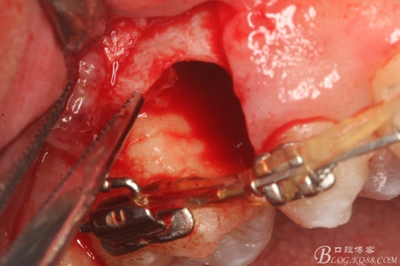

圖18.取出近中部分后,接著挺松15牙根的遠中部分

圖19.挺松后,15的遠中部分仍從合面狹小間隙通過取出。

圖20.取出的15遠中部分

圖21.相鄰牙齒毫發(fā)無損,牙槽窩形態(tài)正常,無破壞。